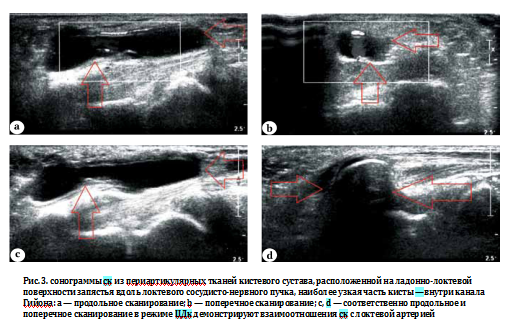

У параартикулярных кист «ножка» заканчивалась в периартикулярных тканях, или киста непосредственно располагалась на связке (характерно для кист, расположенных на кольцевидных связках пальцев кисти). при визуализации сухожильных ск выявлялась непосредственная связь полости кисты с сухожильным влагалищем. полость кистевого сустава от СК отличала его более глубокое расположение и большой объем (рис. 3).

Используя технику дозированного сдавления датчиком, относительно несжимаемую синовиальную кисту, заполненную густой вязкой жидкостью, дифференцировали с теносиновитом, при котором жидкость легко перемещалась вдоль сухожильного влагалища.